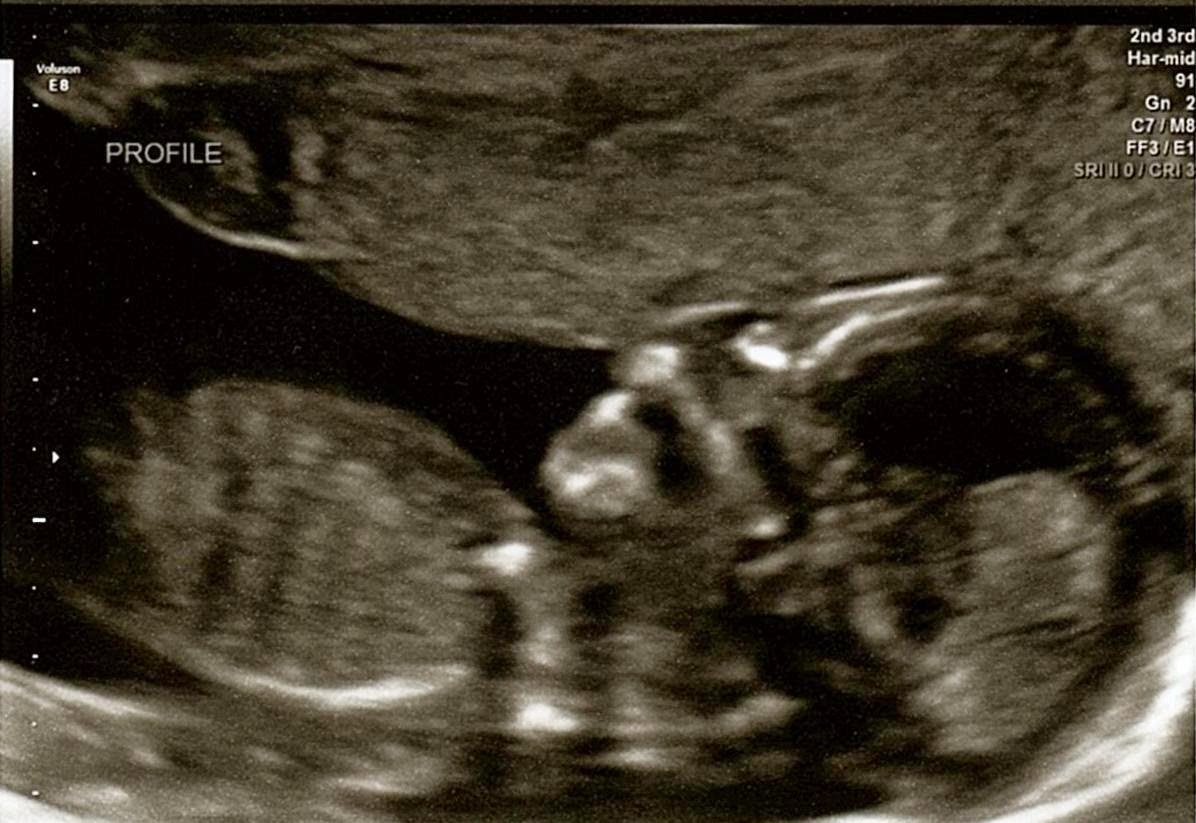

Here's one of the latest sonograms of our little one. We were lucky to catch him mid-yawn!